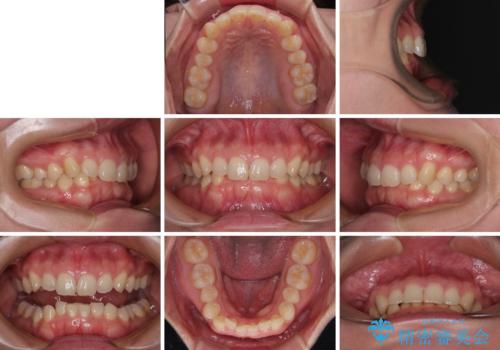

隠れた前歯が気になる ディープバイトのワイヤー矯正治療

- 下顎前歯が完全に隠れてしまっていることを気にして来院された患者様です。

下顎の臼歯が手前に傾斜していることで咬み合わせが深くなってしまい、下顎前歯が見えないほどに上顎前歯が覆い被さっている状態でした。

咬合力が強いことと、マウスピースを長時間装着する自信がないとのことで、ワイヤー装置にて矯正治療を行うこととしました。

下顎臼歯を起き上がらせるためにユーティリティーアーチを使用し、一気に深い咬み合わせを改善することができました。